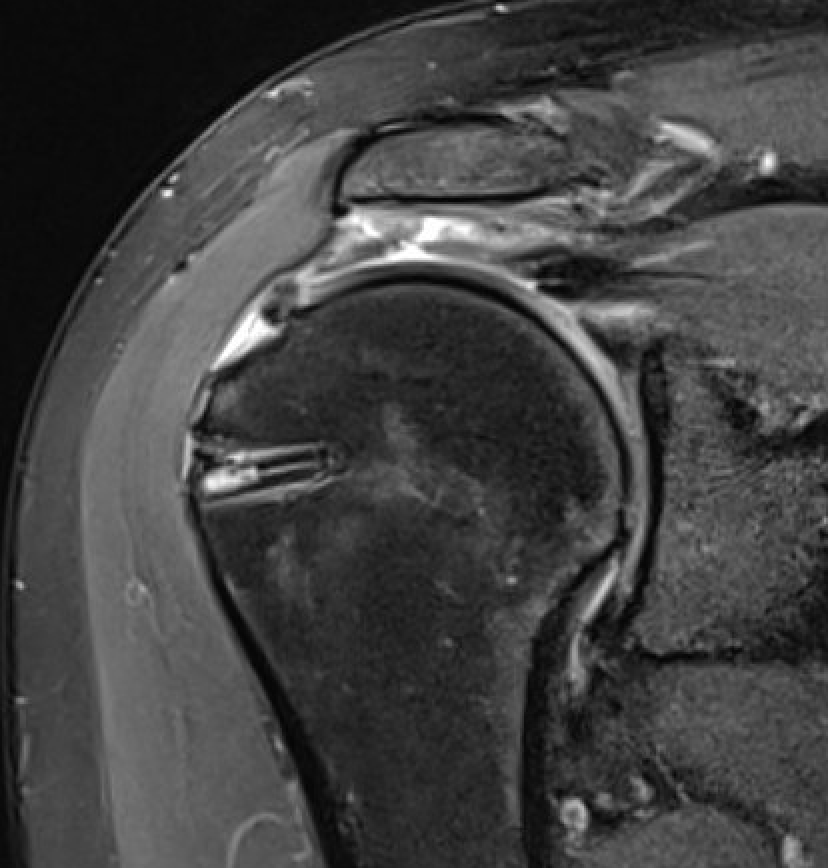

Full thickness tears

Supraspinatous Tear Minimal RetractionSS tear arthroscopyArthroscopic Suture Bridge Cuff Repair

Arthroscopic Supraspinatous Repair